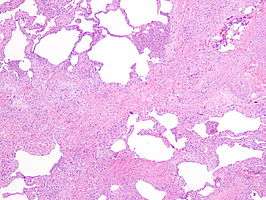

Appearance of usual interstitial pneumonia (UIP) in a surgical lung biopsy at low magnification. The tissue is stained with hematoxylin (purple dye) and eosin (pink dye) to make it visible. The pink areas in this picture represent lung fibrosis (collagen stains pink). Note the "patchwork" (quilt-like) pattern of the fibrosis.